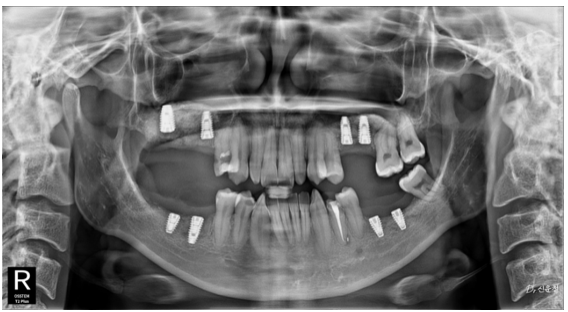

임플란트, 신경치료, 사랑니 발치는

하루 만에 끝나는 치료가 아닙니다.

촬영일 : 250526

임플란트 → 뼈와 단단히 붙는 시간 필요

신경치료 → 보철 제작 기간 필요

결혼 날짜를 기준으로 치료 일정을 역산해 계획을 세워야 합니다.

촬영일 : 251117 (임플란트 총 8개 식립 상태)

한 달 전이라면

선택할 수 있는 치료 범위는 상당히 줄어듭니다.

하지만 3~6개월 전이라면

충분히 계획적으로 진행할 수 있습니다.